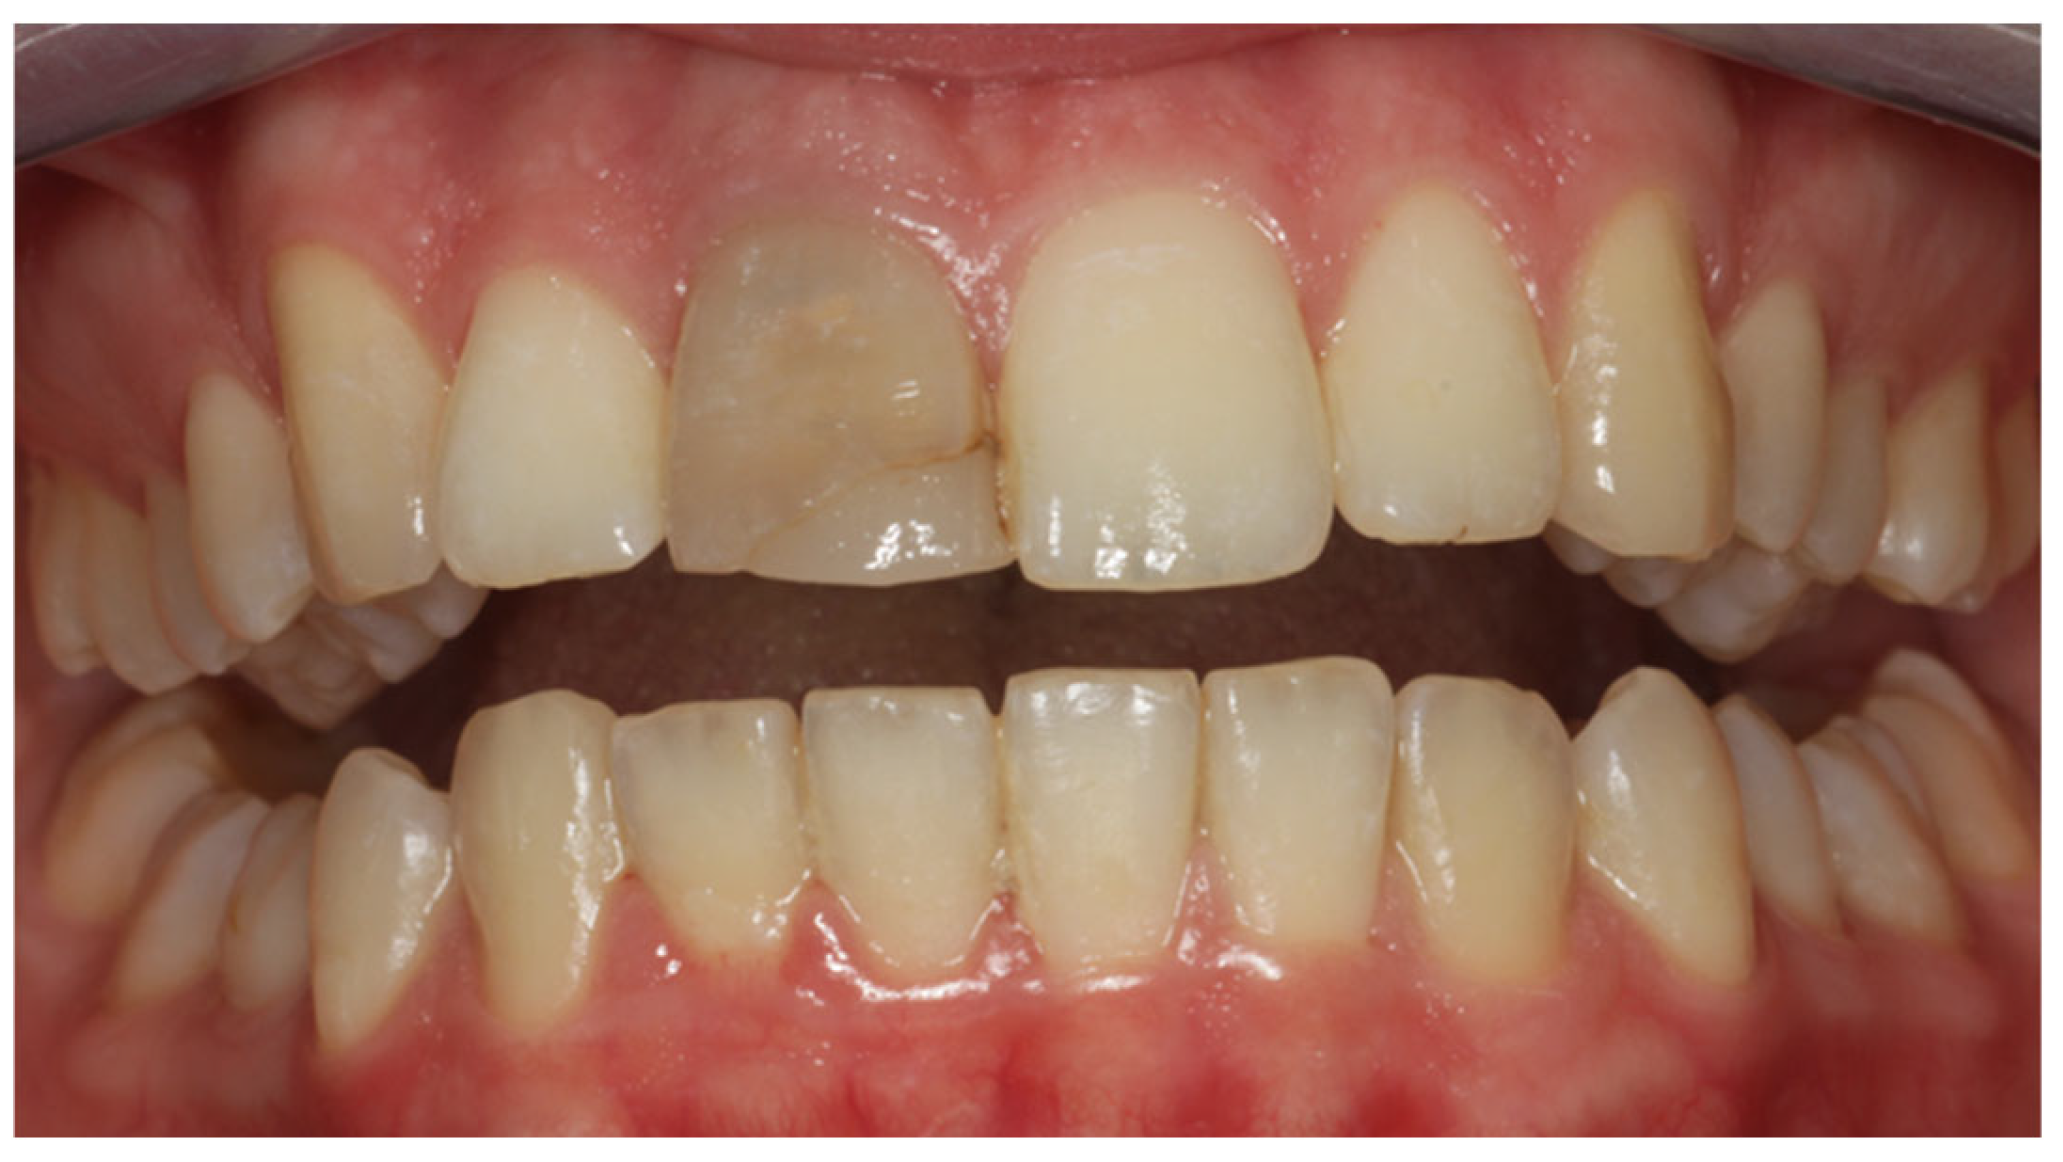

2. Clinical Case

- Porcelain veneers provide a reliable and conservative procedure for the aesthetic restoration of endodontically treated teeth that have undergone discoloration.

- For better aesthetic results, in cases of intrinsic discoloration, an internal tooth bleaching procedure may precede.